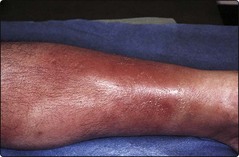

Cellulitis

Cellulitis is an infection of the subcutaneous tissues. It is often due to streptococci, but is deeper and more extensive than erysipelas. The cardinal features are swelling, redness and local pain with systemic upset and fever. The leg is often affected (Fig. 5). The organism may gain entry through fissures between the toes or via a leg ulcer. Lymphangitis is common, and lymphatic damage may result. Hospital admission is usually indicated, particularly if the leg is involved. Antistreptococcal antibiotics are given for straightforward cases. However, a broad-spectrum antibiotic is prescribed for cellulitis complicating a leg ulcer, because a selection of organisms may be responsible. Blood cultures and ulcer swabs may give some guidance.

Fig. 5 Cellulitis affecting the lower leg.